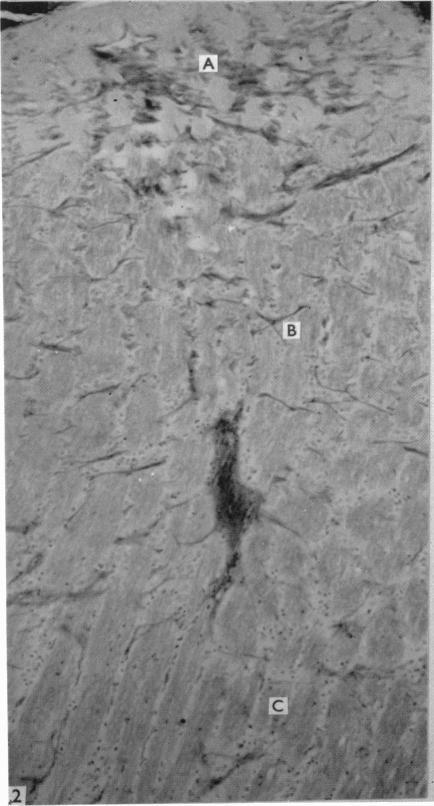

Electron microscopic study of demyelination in an experimentally induced lesion in adult cat spinal cord.

J Biophys Biochem Cytol. 1960 Jul;7(4):685-96. doi: 10.1083/jcb.7.4.685.